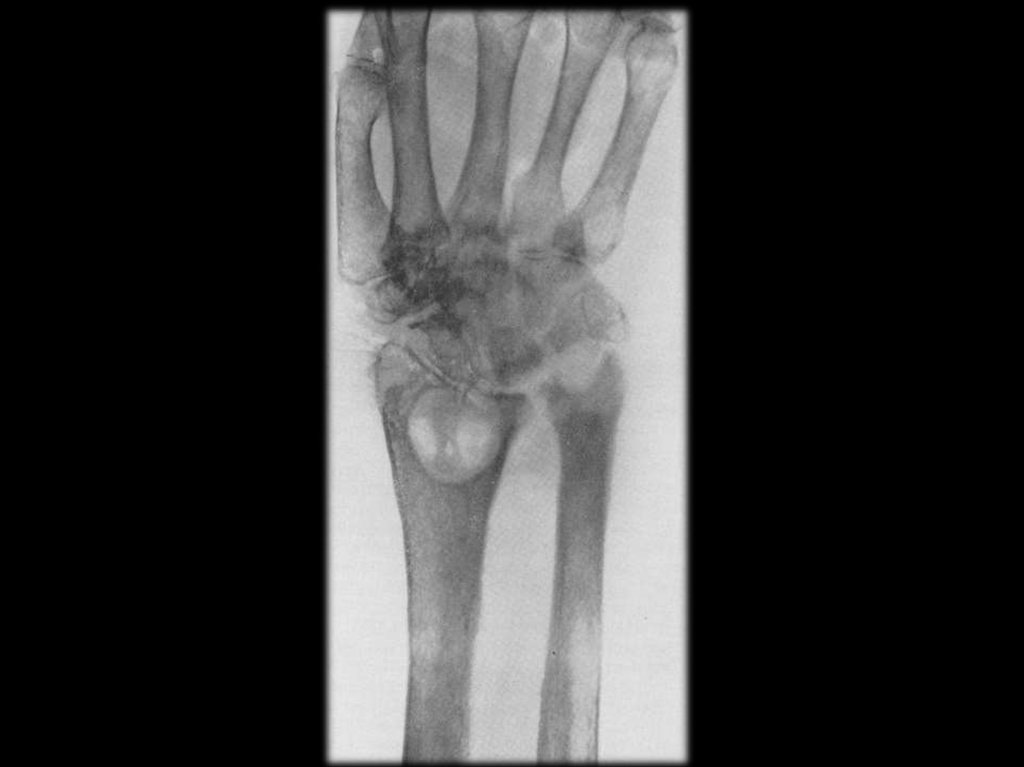

Динамика рентгенологических изменений в

области суставов при хроническом сифилисе

Сифилитический артрит левого коленного

сустава, контрактура